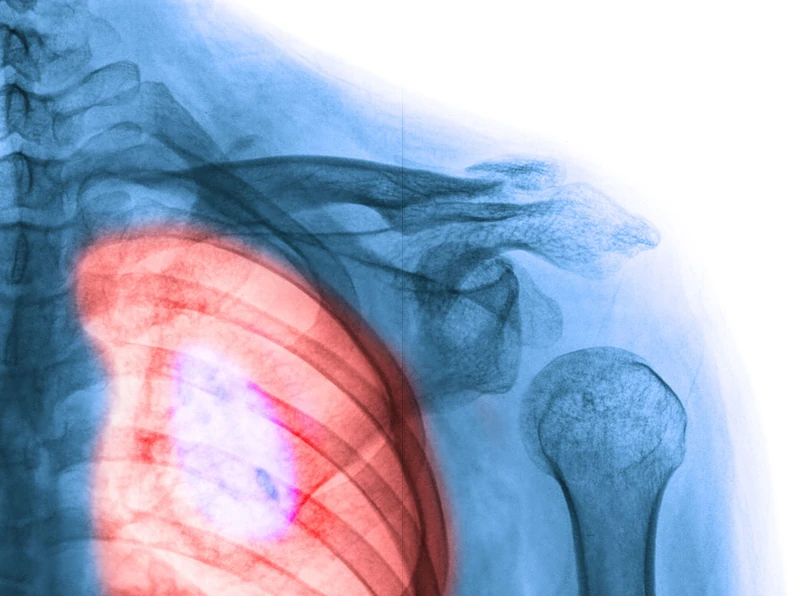

Przede wszystkim nie palić i unikać przebywania w towarzystwie osób palących. Ryzyko zachorowania na raka płuc zmniejsza się o połowę już po 5 latach od momentu rzucenia palenia, a po 10-15 latach jest ono takie jak u osób, które nigdy nie paliły. W Polsce (i w większości państw świata, nawet tych najbogatszych) nie prowadzi się powszechnych badań przesiewowych w kierunku raku płuca, można je natomiast wykonać samodzielnie. – Podstawowym badaniem diagnostycznym zalecanym przy podejrzeniu raka płuca jest badanie RTG klatki piersiowej w projekcjach przednio-tylnej i bocznej, które pozwala zobrazować nieprawidłowości typu cienia okrągłego, zmiany zarysu wnęki, zaburzeń powietrzności o charakterze rozedmy lub niedodmy, czy zmiany naciekowej. Jednakże prawidłowy wynik konwencjonalnego badania rentgenowskiego klatki piersiowej nie wyklucza nowotworu, który może być umiejscowiony w okolicach o ograniczonej dostępności (np. szczyt płuca lub śródpiersie). W takiej sytuacji zalecane jest również wykonanie badania tomografii komputerowej z kontrastem dożylnym. Należy jednak pamiętać, że nie ma jednoznacznych zaleceń co do rytmu wykonywania takich badań obrazowych. Trzeba zachować czujność i wykonywać badania obrazowe (rentgen klatki piersiowej czy tomografia komputerowa) w przypadku wystąpienia niepokojących symptomów, co szczególnie tyczy się osób aktywnie palących – tłumaczy lek. Małgorzata Stelmaszuk, onkolog, Magodent, Grupa LUX MED.